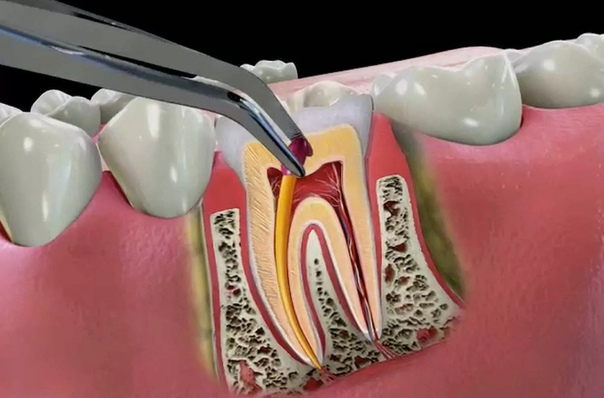

на 1-ом этапе стоматолог должен удалить из корневого канала продукты воспаления мягких тканей зуба или старый пломбировочный материал.

Это сможет обеспечить выход гноя из гранулёмы (или кисты) и из корневого канала. Нередки случаи, когда необходимо расширить корневой канал. Чтобы это сделать, врачи-стоматологи используют специальные свёрла, а иногда делают микроразрез в десне; второй этап включает комплекс мер по чистке и промывании каналов антисептиками, контролю переносимости пробы на герметичность. Приёму восстановительных препаратов; на заключительном этапе врачу-стоматологу остаётся запломбировать корневой канал и кариозную полость. Пломбирование осуществляется только после того, как острые воспалительные ощущения стихнут, а само воспаление спадёт.

Лечение в острой форме подразумевает избавление от сильных болей, причиняющих дискомфорт. Процедура начинается с очистки корневых каналов от остатков пульпы, что позволяет экссудату свободно вытекать, снижая давление гнойных масс внутри десны. В осложненных ситуациях, когда данной меры недостаточно, специалист может прибегнуть к разрезанию мягких тканей в районе верхушки корня и установке дренажа. Для предотвращения распространения инфекции, выделяющейся вместе с гноем, пациенту назначается пероральный прием антибиотиков.

При верхушечном периодонтите врач производит инструментальную обработку корневых каналов, удаляя пораженные участки тканей. Затем осуществляется введение лекарственных препаратов, и пломбирование.

Лечение периодонтита состоит из ряда отдельных этапов, количество и последовательность которых непосредственно зависит от стадии. Терапия острой стадии требует как минимум трех посещений кабинета зубного врача. На первой — доктором производится расширение корневого канала механическим способом: прочистка и удаление остатков пораженных участков и полная антисептическая обработка. Оставшийся гной свободно выходит через образовавшуюся полость в зубе, а обработанный участок защищается от попадания пищи при помощи специальной пародонтальной повязки.